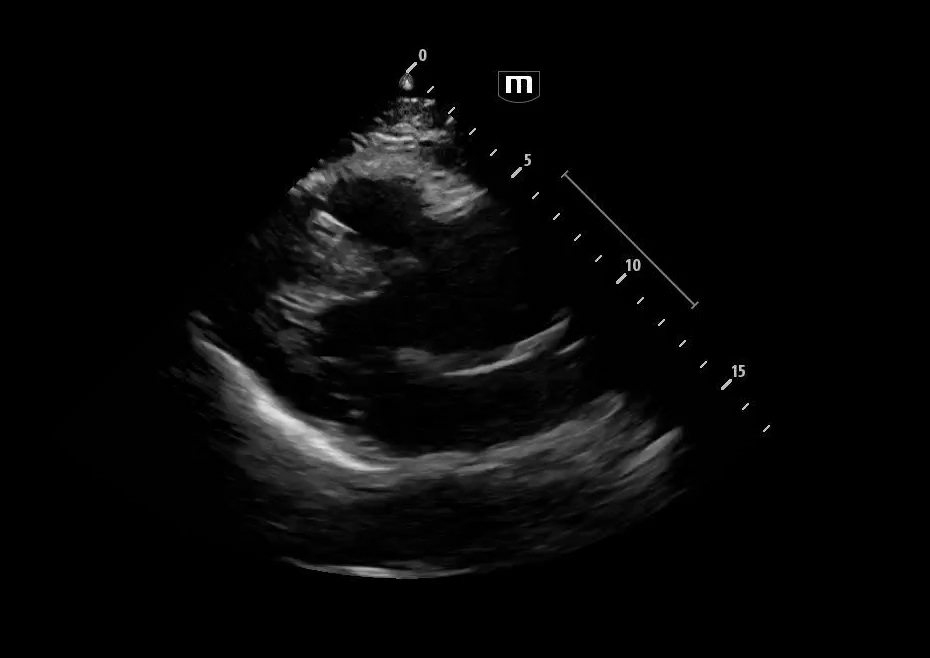

Image 1 & 2: Parasternal long axis

Interpretation: Parasternal long-axis view demonstrating marked dilation of the aortic root, measuring approximately 5.1 cm, concerning for proximal aortic pathology. Preserved EF and no effusions noted.

Teaching point:

• Normal aortic root diameter: < 3.7–4.0 cm

• A diameter >4 cm should raise concern for aneurysm or dissection